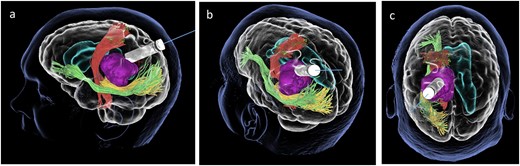

Subsequently, a tsMIPS approach was performed through the intraparietal sulcus. A tubular retractor (NICO BrainPath®) was cannulated 30 mm deep, directly onto the lesion. Following docking of the tubular retractor, an intra-operative CT scan (O-ARM®) was performed, and the resulting images were fused with pre-operative MRI and tractography. The port was identified at the centre of the lesion, with air acting as contrast (Fig. 3). The tumour was centrally debulked, outer sides rolled inwards, and capsule disconnected.

Coronal (a), sagittal (b) and axial (c) views of the merged images from intra-operative CT scans (O-Arm) with pre-operative MRI tractography. The tubular retractor is in situ. (d) Virtual 3D reconstruction of the tubular retractor (brown) in the merged images and its relationship with the tumour (purple), the CST (red), the IFOF (green), and the OR (yellow).

In this case, we demonstrate the use of intraoperative CT imaging coupled with pre-operative MRI and cortical (TMS) and subcortical (tractography) brain mapping for localization of a tubular retractor during tsMIPS to an intraventricular lesion. This technique provides an accurate localization of the tubular retractor port, allowing for safe resection of this deep tumour and 3D visualization of the tubular retractor and its relationship with the lesion and the pre-operative mapping.

Conventional methods of neuronavigation using optical or electromagnetic neuronavigation techniques are commonly employed in neurosurgical oncology, and have been shown to improve outcomes for patients [9]. Neuronavigation is a critical adjunct in tsMIPS where it is used to control the trajectory as the retractor is pushed through the sulcus and towards the lesion [10]. Despite being useful, these modalities are limited as they only provide a unidimensional view of a location at any given time. Moreover, electromagnetic navigation systems can interfere with IONM, causing noise in the acquisition of MEPs [11]. With air acting as a contrast agent, intraoperative CT provides an additional advantage as the location of the tubular retractor can be visualized in three dimensions.